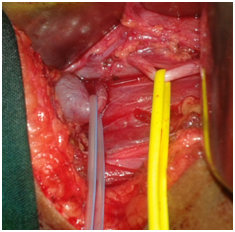

We decided to operate this child in view of the increased hydronephrosis. Child underwent open surgical intervention via right upper abdominal transverse incision. On exploration the ureter was found to dip behind the inferior vena cava after circumscribing the vessel it pursued its normal course, below the bifurcation of the iliac vessels (Figures 3&4).

Figure 3 Intraop pic –IVC & Retro due to retrocaval ureter.

Figure 4 Rt hydroureteronephrosis cavalureter.